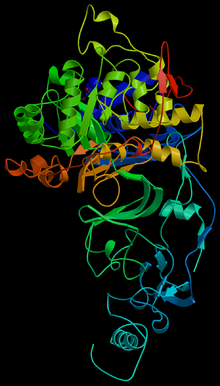

The cagA gene codes for one of the major H. pylori virulence proteins. Bacterial strains that have the cagA gene are associated with an ability to cause ulcers. The cagA gene codes for a relatively long (1186 amino acid) protein. The cag pathogenicity island (PAI) has about 30 genes, part of which code for a complex type IV secretion system. The low GC-content of the cag PAI relative to the rest of the Helicobacter genome suggests the island was acquired by horizontal transfer from another bacterial species.

The type IV secretion apparatus also injects the cag PAI-encoded protein CagA into the stomach's epithelial cells, where it disrupts the cytoskeleton, adherence to adjacent cells, intracellular signaling, cell polarity, and other cellular activities. Once inside the cell, the CagA protein is phosphorylated on tyrosine residues by a host cell membrane-associated tyrosine kinase (TK). CagA then allosterically activates protein tyrosine phosphatase/ protooncogene Shp2. Pathogenic strains of H. pylori have been shown to activate the epidermal growth factor receptor (EGFR), a membrane protein with a tyrosine kinase domain. Activation of the EGFR by H. pylori is associated with altered signal transduction and gene expression in host epithelial cells that may contribute to pathogenesis. It has also been suggested that a C-terminal region of the CagA protein (amino acids 873–1002) can regulate host cell gene transcription, independent of protein tyrosine phosphorylation. There is a great deal of diversity between strains of H. pylori, and the strain with which one is infected is predictive of the outcome.